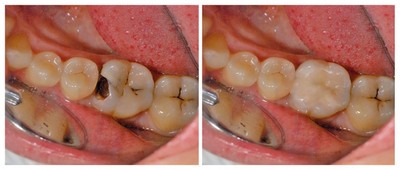

- Запущенный кариес — основная из них. С течением времени без необходимого лечения кариозная полость продолжает расширяться и углубляться, из-за чего патогенные бактерии легко проникают в мягкую зубную ткань. Проникновение происходит как напрямую, если пульпа открыта, так и по дентинным каналам.

- Неполное удаление кариозных участков в процессе лечения зуба. Под пломбой бактерии продолжают разрушать зубные ткани и достигают пульпы.

- Низкий уровень гигиены ротовой полости, что неизбежно приводит к кариесу.

Своевременное и безотлагательное лечение кариеса — основная профилактика пульпита. Но даже, на первый взгляд, благополучно запломбированные зубы не являются поводом игнорировать регулярные профилактические осмотры.

У каждого пломбировочного материала существует определённый срок годности, по истечении которого он начинает разрушаться. Усадочные деформации образуют зазоры, куда беспрепятственно проникают микроорганизмы, существующие при самой тщательной гигиене ротовой полости.